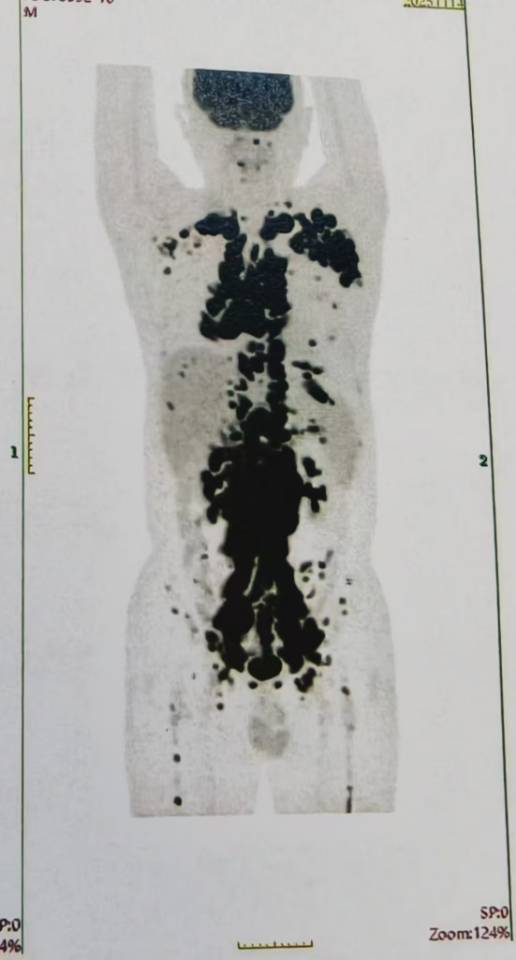

最好的礼物是CR回家过年!我今年38岁,滤泡一直规范治疗但还是转化成弥漫大B淋巴瘤了,双表达型。经过评估参加了16周期的双抗临床试验,可等来的不是完全缓解……而是疾病进展。而且进展的非常快,我喘不上气,躺不平,睡不着。12月初的北京很冷,我觉得这个春节应该是和我无缘了……怀着一丝侥幸希望,我来到了北京陆道培医院。柳喜洋主任看了看我的病历说“你们若信任,我们便全力以赴!”12月3号我们住院了,做了血液和超声等检查。柳主任说我肝功能受损严重,乳酸脱氢酶飙到了2849。双侧胸腔也有大量的积液,左边最深的地方11.5公分。她说那是肿瘤侵犯了多浆膜腔。全身摸得到的地方,淋巴结都是肿大的……柳主任医生团队立刻采细胞,并商量桥接治疗方案,苏敏护士长团队也还一遍遍的安慰我给我加油打气!治疗刻不容缓争分夺秒,桥接后就回输CD19/22 双靶点CART。之后的日子是CART细胞在我体内战斗的日子,我的家人和医护团队也24小时紧张细心的守候着。我也一遍遍的告诉自己要坚持打赢这场仗,我要回家过年!终于回输的第28天,PET CT结果出来了!柳主任洪亮的声音整个病房都听得到:“凯凯恭喜你,CR啦!”曾经那个全身淋巴结肿得像挂了一串串葡萄的我,那个躺不下、睡不着、被胸水压得透不过气的我——被拽回来了。我这医路走来有多少难,心里就有多少的感恩!谢谢柳喜洋主任,苏敏护士长,谢谢所有的医护团队!没有什么比回家过年更好的新年礼物了!小年那天我们在家就吃上了热热乎乎饺子,如今写下感谢的话语,还有送去我的祝福给所有在治疗的病友,祝大家都能CR回家过年!